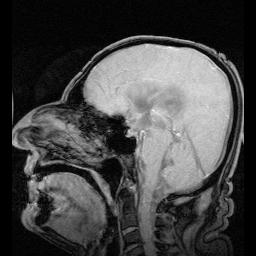

• Функціональне МРТ (fMRI) для візуалізації кровообігу й ліквору.

Результати показали: після безсонної ночі реакції були повільніші, частіше траплялись «провали уваги». Саме в ці моменти фіксувались хвилі ліквору й хвилі мозкової активності, подібні до стадій N1–N2 неглибокого сну.